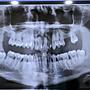

[問題] 拔智齒

剛拔完智齒現在整個嘴巴都張不開... 由於智齒長得太深 醫生是用鋸子鋸開 然後再逢合…除了吃冰和流質食物外我還需要注意蛇們嗎? 要很久才會好嗎? -- ※ 發信站: 批踢踢實業坊(ptt.cc) ◆ From: 211.72.1.234